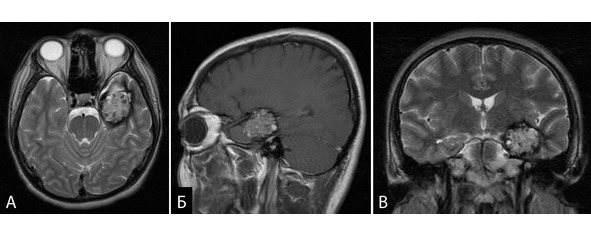

В послеоперационном периоде у больного развилась правосторонняя гемиплегия, тотальная афазия. При КТ данных за геморрагические осложнения не выявлены, выявлен ишемический очаг в подкорковых структурах слева, типичный для повреждения передней ворсинчатой артерии (рисунок 36).

Рисунок 36. Клиническое наблюдение 6. Послеоперационное КТ больного, аксиальная проекция. Виден формирующийся крупный гиподенсивный очаг в области подкорковых структур слева. А, Б – без контрастного усиления. В, Г – с контрастным усилением.

Больной находится под наблюдением в течение двух лет после операции. Эпилептические приступы не повторялись. К настоящему моменту наблюдается некоторое восстановление движений в правых конечностях, однако состояние можно по прежнему оценить как тяжелая инвалидизация (4 балла по шкале Rankin).

Случай демонстрирует возможность тяжелых осложнений хирургического лечения при относительно «благоприятной» для удаления локализации.